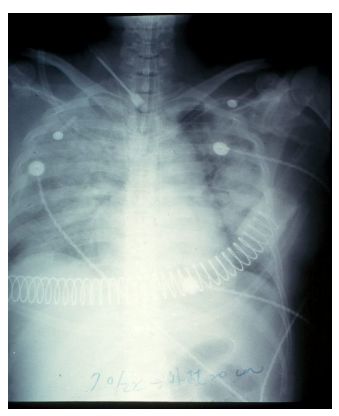

經過三天抗生素治療,病人呼吸狀況並無起色,FiO2 調高至 80%, PaO2:62mmHg, SpO2:90%,追蹤之 CxR 顯示 bilateral diffuse infiltration。Bp: 89/49 mmHg, HR:142/min。Ventilator setting: Tidal volume 520 ml, PEEP 8 cmH2O, I:E ratio 1:2, respiratory rate 20/min

61b80be63738f.jpg